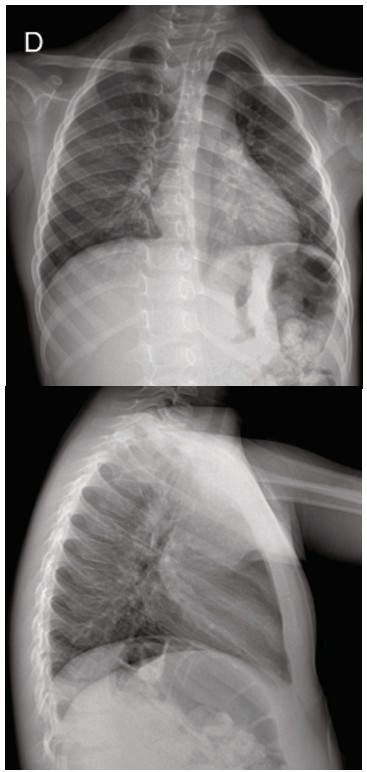

Figure 2. Chest X-ray at day 3 of admission.

Chest X-ray (PA view) report: cardiac silhouette is within normal limits. Mild bilateral thickening of the peribroncovascular interstitium in the perihilar and basal regions bilaterally. No airway consolidations are observed. Costophrenic and cardio phrenic angles are clear.

The patient was admitted to the hospital with a presumptive diagnosis of an acute lower respiratory infection. Oxygen requirement was low (0.5- 1 L/min), respiratory distress was rapidly released and clinical findings consistent with acute asthma were never present. However, the peculiar high-pitched bilateral rales persisted, sounds that were not found in previous admissions and office visits when the patient had respiratory infections or acute asthma. Due to this finding, further investigation was conducted through an interview with the parents, and a key detail emerged: the patient had been participating in daily swimming lessons at an indoor pool with no ventilation. Most notably, on the day the symptoms began, the pool had been freshly chlorinated, just before the lesson and a hard chloride smell was noted. Moreover, during the class, an attempt by the swimming instructor to teach the patient to float resulted in a brief submersion, leading to coughing, red eyes, respiratory difficulty, and the subsequent development of his symptoms. Therefore, the presumptive diagnosis was revised to chlorine-induced chemical pneumonitis and treatment was adjusted by incorporating prednisone. By day 3, the patient maintained adequate oxygen saturation and had been without supplemental oxygen for 24 hours. On physical examination, the respiratory rate averaged 24 breaths per minute (50th percentile for age). Bilateral breath sounds were preserved, with mild fine rales noted. A follow-up chest X-ray revealed mild bilateral thickening of the peribronchovascular interstitium, primarily in the perihilar and basal regions (Figure 2). Given the patient’s favorable clinical status, he was discharged with prednisone, salbutamol and his regular medication regimen. A follow-up consultation after discharge was unremarkable.